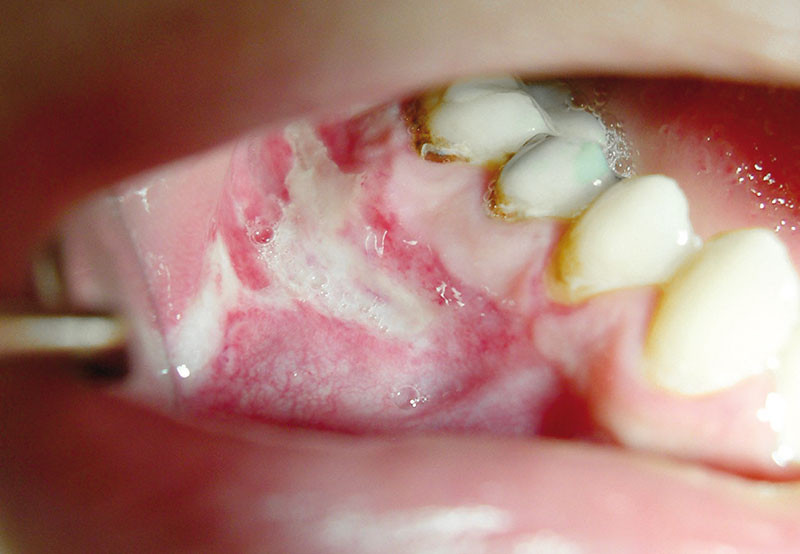

Oral Ulceration Clinician's Brief

From www.cliniciansbrief.com

Oral Ulceration Clinician's Brief Toothpaste Oral Ulceration Minor aphthous mouth ulcers are the most common (8 in 10 cases). Drink through a straw (especially acidic drinks like coffee, soda, and fruit juice) to. Toothpaste or mouthwash that contains sodium lauryl sulfate (sls) an allergic response to oral bacteria. Do not use toothpaste containing sodium lauryl sulphate. Drink cool drinks through a straw. Use a soft toothbrush to. Toothpaste Oral Ulceration.